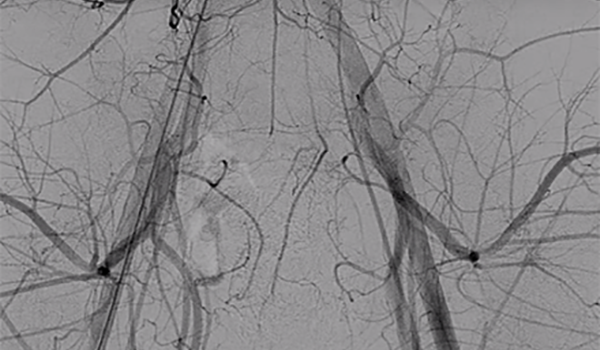

Direxion™

and Direxion HI-FLO™ Torqueable Microcatheters

Case Study Downloads